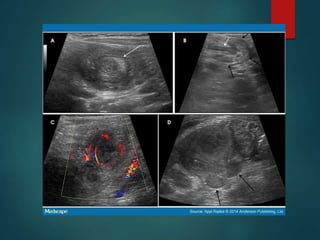

Ultrasound • Reversal ofthe normal anatomic relationship between the SMA and • “whirlpool sign” - midgut volvulus.